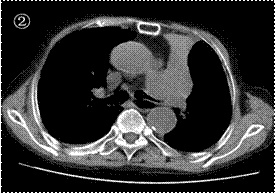

例2:患者男性,88岁,是一位“慢阻肺”患者,近期因出现“咳嗽、呼吸困难加重伴咯血”于2021年5月14日入院。胸部CT提示左主支气管内及左肺门肿块、左上肺完全不张(图1、2)。对于这位超高龄慢阻肺患者本来就已经呼吸困难了,左肺长了一肿瘤同时伴气管内堵塞,无疑是雪上加霜,因此入院后呼吸困难进行性加重,如果不积极处理患者很快进入呼吸衰竭而损失生命,好在患者子女要求积极治疗。同样对于这例88岁的超高龄慢阻肺同时伴有肿瘤的患者,救治工作之困难可想而知,但是我们没有放弃,同样制定了周详细致的诊疗计划。

例1:患者男性,85岁,因“咳嗽、咯血、呼吸困难半月”于2021年4月23日入院。胸部CT提示左肺门巨大肿块同时导致左肺完全不张(图1、2)。入院后发现患者呼吸非常困难,在高流量吸氧情况下血氧饱和度都不能维持,并出现神志不清,为了暂时抢救患者生命,于2021年4月24日晚上行气管插管,用呼吸机辅助通气。查支气管镜检查证实了左主支气管下段巨大新事物形成,表面覆盖坏死物,完全堵塞管口。其实这一情况对于大多数患者家属来说都可能会放弃治疗而自动出院的,但是这位老人的子女非常孝顺,要求我们积极抢救以延续患者生命。对于如此严重的超高龄晚期重症肺癌患者,尽管救治工作非常非常困难,但是我们还是制定了详细的治疗方案。